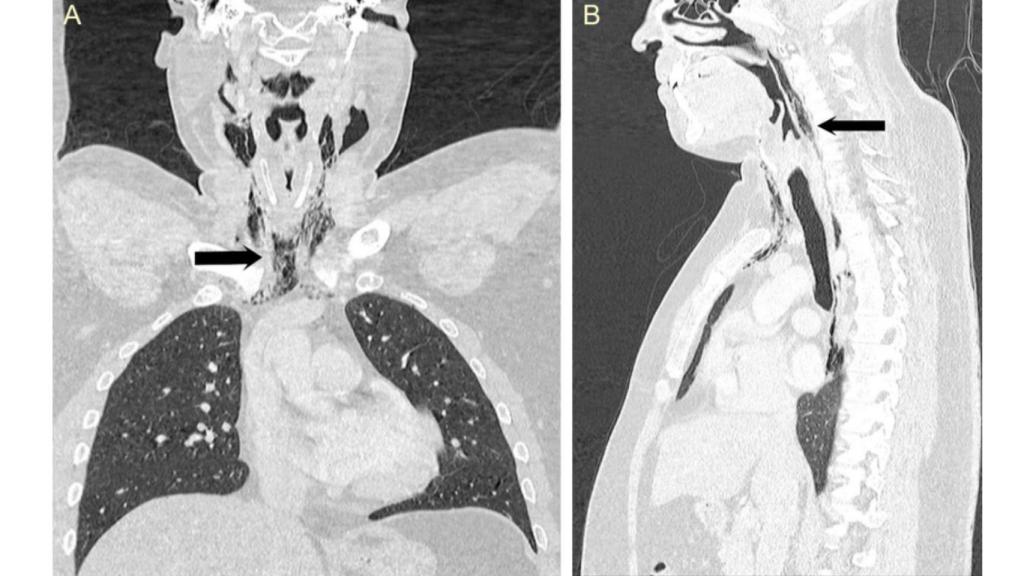

Los enfisemas localizados en el cuello y pecho del paciente.

Los enfisemas localizados en el cuello y pecho del paciente. Yang W, et al. BMJ Case Rep 2018.

La inspección médica reveló un crepitar en su respiración, un sonido burbujeante de su cuello a su caja torácica que indicó a los especialistas que se había infiltrado aire en su tejido y músculos del pecho. Una tomografía confirmó la presencia de enfisemas - bolsas de aire - en su cuello, en las zonas de la tráquea y la laringe. También se observó la presencia de neumomediastino, la infiltración de aire en el mediastino, la región torácica entre ambos pulmones.

El equipo de cirugía oral y maxilofacial dirigido por la doctora Wanding Yang determinó que se había desgarrado la faringe por bloquearse las vías aéreas al estornudar a la altura del seno piriforme. Esta ruptura de la parte posterior de la garganta ya había sido observada como consecuencia de un trauma violento provocado por tos intensa, vómito o náuseas, pero es la primera vez que se describe como efecto de un estornudo. La situación era grave: el paciente corría el riesgo de contraer una infección tanto en el cuello como en el tórax (mediastinitis).